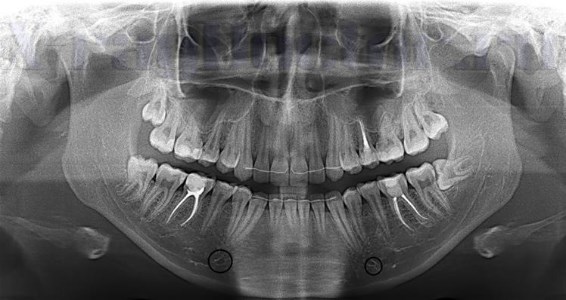

Для данной разновидности периодонтита зачастую характерно бессимптомное течение, что существенно затрудняет диагностику. Объективно выявляется изменение цвета коронки в результате нарушения трофики. Полость глубокая, а канал заполнен путридными массами с гнилостным запахом (они образуются при распаде пульпы). Зондирование и перкуссия безболезненны, а температурная реакция отсутствует. Основанием для постановки диагноза в данном случае является рентгенологическая картина.

На снимке определяется расширение периодонтальной щели в зоне апекса.

На рентгеновском снимке заметно изменение структуры цемента и дентина в области апекса и нечетко очерченный очаг разрежения костной ткани.

На снимке видно разрежение костной ткани с резкими отчетливыми контурами. По бокам от корня может иметь место гиперцементоз, а в области верхушки – деструкция твердых тканей.

Клиническими признаками являются постоянная боль, нарастающая при накусывании, отечность окружающих мягких тканей (в частности – сглаживание по переходной складке), их гиперемия, а также уплотнение и болезненность регионарных лимфоузлов. Симптоматика нарастает постепенно. Объективно определяется безболезненность при зондировании канала (он заполнен некротическими массами), резко положительная реакция при вертикальной перкуссии и умеренная болезненность при постукивании в горизонтальном направлении. Зуб может быть подвижен, и чаще всего он отличается по цвету от здоровых. Реакция на горячее и холодное – отрицательная. На рентгеновском снимке четко видны участки разрежения костной ткани с нерезкими контурами.